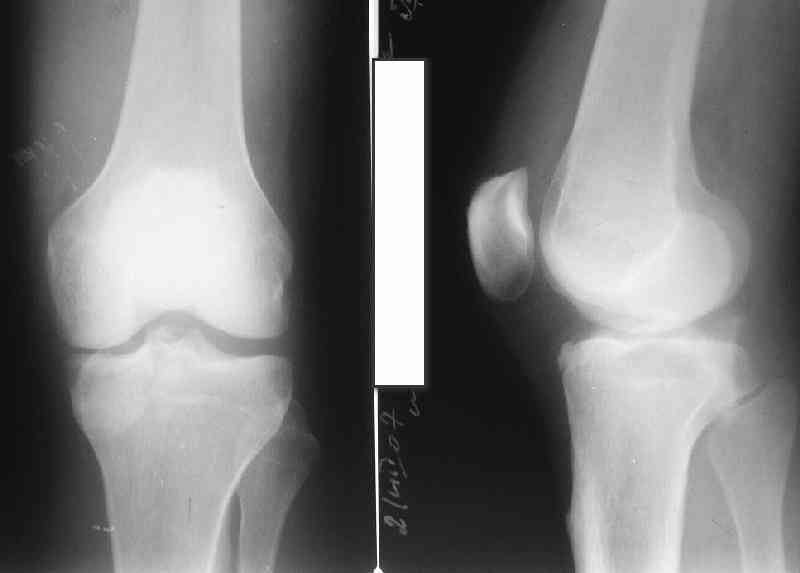

Based on the images ( it would be nice to have axial cuts),it seems to be posteromedial fragment, almost all the way into

posterior portion of the tibial eminance.

Approach: posteromedial, but you have to open the joint, since the fragment is small and there will be an issue with the

medial meniscus ( likely torn).

The appearance of the fragment is indicative of a shearing injury, so you will need small screws ( hand set ) that will

have to be subchondral, or, start from the back and transfix the fragment going into anteroinferior direction. MRI might be

sometimes useful to assess integrity of the ligaments. I hope there is no vascular issues.